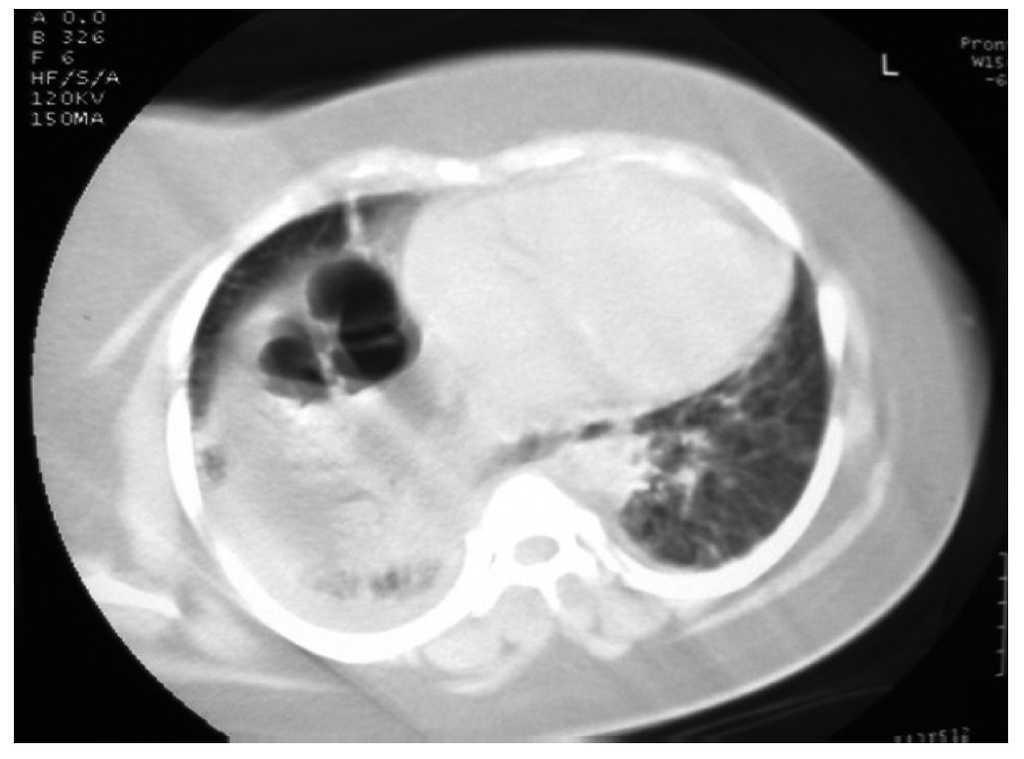

La tomografia computada del tòrax va confirmar els diagnòstics d'hèrnia intestinal a través del diafragma i d'infiltració. La localització i la morfologia de l'hèrnia s'ajustaven a HM (fig. 2). La pacient va ser traslladada a la unitat de cures intensives (UCI) per continuar amb l'elaboració del diagnòstic.

Figura 2 El diagnòstic es confirma per mitjà de tomografia computada.